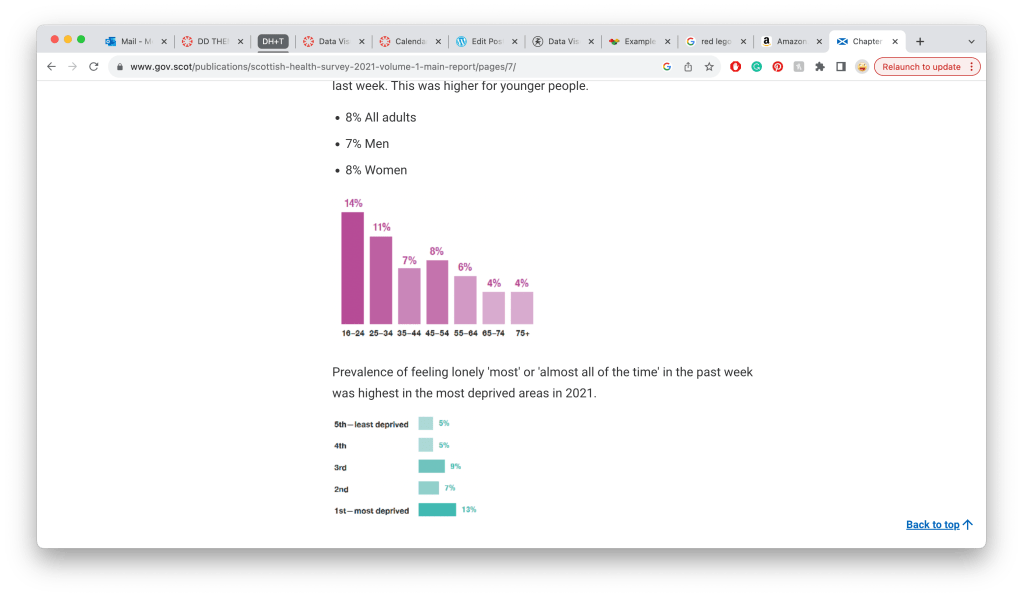

https://www.gov.scot/publications/scottish-health-survey-2021-volume-1-main-report/pages/7/